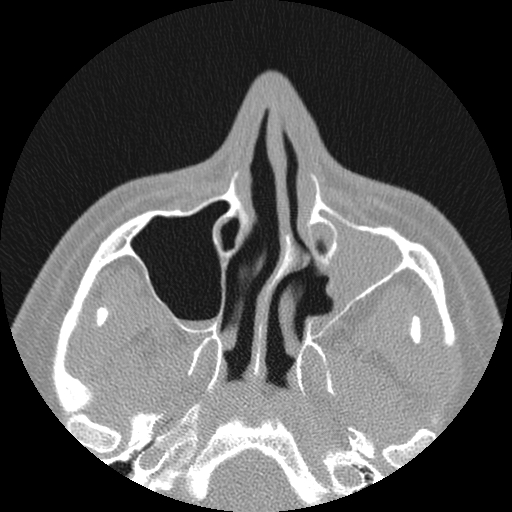

Here are a few shots illustrating how off-kilter my septum is. That line right down the middle is the septum, and it is supposed to be pretty straight. Mine, however, veers off to the left side of my body (the right in the pictures), includes a funky hook-shaped spur, and the whole nasal space is sort of off-kilter and asymmetrical. But it’s nothing that a little modern medicine can’t fix. The last picture has nothing to do with my septum, but I think it’s the coolest image on the my entire C/T scan disk.